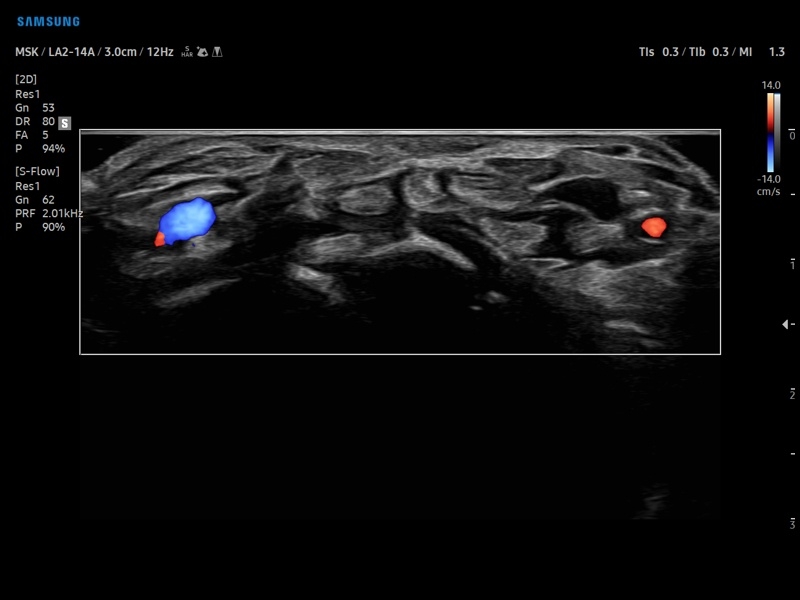

• Ангиология

• Диагностика костно-мышечной системы

• Модуль MV-Flow – программа (режим), позволяющая визуализировать кровоток в микроциркуляторном русле с высоким разрешением без использования контраста.

• Модуль LumiFlow – программа отображения кровотока с объемной графикой для лучшего понимания архитектоники сосудистого русла.

• Программа SEE Stream – режим недопплеровской визуализации кровотока в реальном масштабе времени.

• Модуль MV-Flow - программа (режим), позволяющая визуализировать кровоток в микроциркуляторном русле с высоким разрешением без использования контраста.